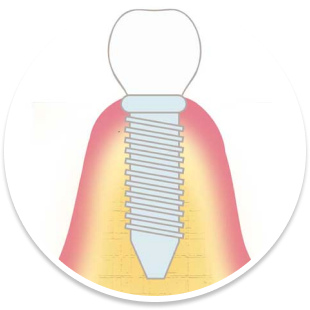

代表的な再生療法のひとつが「GBR(骨誘導再生法)」です。骨が不足した部位に自家骨や人工骨を補填し、特殊な膜(メンブレン)で覆うことで、骨の再生を促しインプラントの土台を築く方法です。

また、上顎奥歯など骨が特に薄い部位には「サイナスリフト(上顎洞底挙上術)」が適応されます。上顎洞と呼ばれる空洞の底を持ち上げ、その下に骨を造成することで、十分なインプラント埋入スペースを確保することが可能になります。

これは、虫歯や歯周病などで抜歯が必要になった際、その当日にインプラントを埋め込む方法です。従来であれば、抜歯後に歯ぐきや骨の治癒を数ヶ月待ったうえで次のステップへ進んでいましたが、この方法を用いることで、治療期間を短縮できるほか、手術の回数も抑えられます。